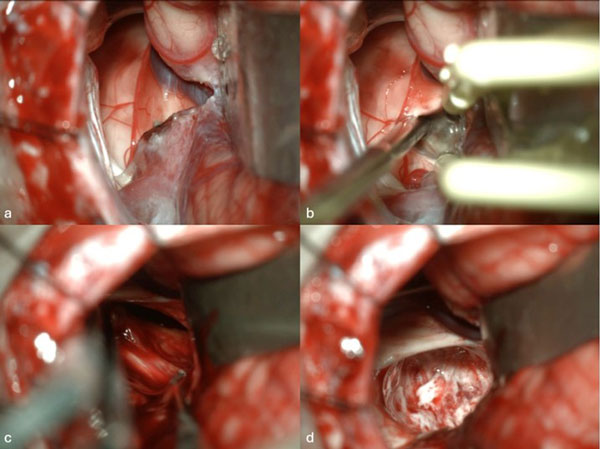

Figura 1. Imágenes intraoperatorias bajo microscopía. Craneotomía suboccipital lateral. Se ingresa al mesencéfalo desde posterior por una ruta supracerebelosa infratentorial lateral. A y B) Corticotomía en surco mesencéfalo lateral. C) Identificación y resección en bloque de la malformación cavernomatosa. D) Revisión del lecho, sin remanente.

Figura 2. RM postquirúrgica de encéfalo. Se evidencia una exéresis completa, sin lesión de estructuras adyacentes. A) Imagen ponderada en T1 posterior a la administración de gadolinio, corte axial. B) Imagen ponderada en T2, corte axial.

Caso 1: cavernoma mesencefálico

Una mujer de 35 años debutó con un cuadro de cefalea asociada a diplopía por parálisis del tercer par craneal izquierdo y hemihipoestesia del hemicuerpo derecho. La RM de encéfalo evidenció una malformación cavernomatosa tegmental izquierda con signos de sangrado reciente. Un año después del sangrado, la paciente fue sometida a una exéresis de la lesión mediante un abordaje suboccipital lateral y supracerebeloso infratentorial izquierdo (Figura 1), logrando una exéresis completa de la malformación (Figura 2). Después del procedimiento, la paciente no presentó nuevos déficits agregados.